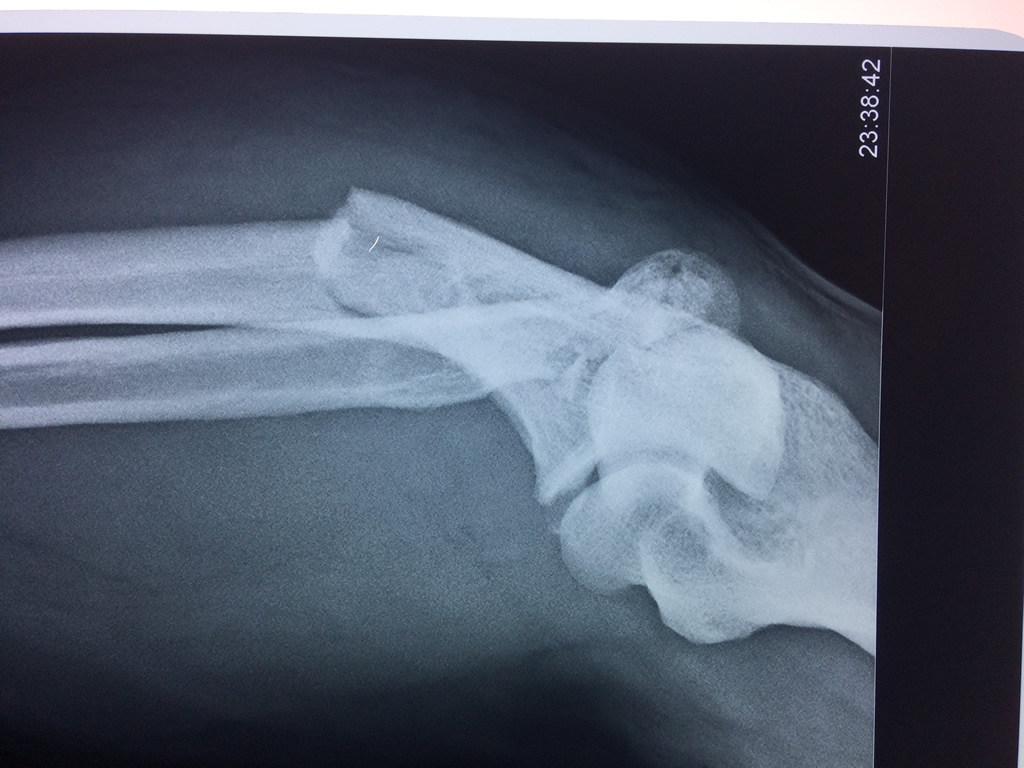

Cirugias en El Salvador - Codo

En anatomía humana, la articulación del codo es la que une el brazo con el antebrazo, conectando la parte distal del hueso húmero con los extremos proximales de los huesos cúbito y radio.

La articulación principal que constituye el codo se denomina humero radio-cubital y puede dividirse en dos partes bien diferenciadas, la articulación humero-radial y la humero-cubital.

Por otra parte el cúbito y el radio forman también una articulación entre si en las proximidades del codo, la cual se denomina articulación radio-cubital proximal.